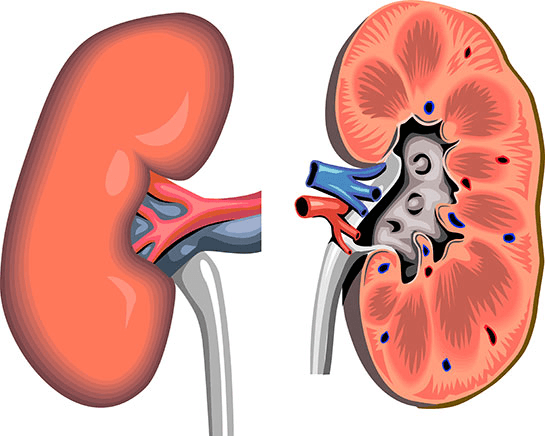

2.3 Viêm thận và suy thận – biến chứng sỏi bàng quang nguy hiểm

Sỏi chặn dòng nước tiểu tại bàng quang thoát ra ngoài dẫn tới tắc nghẽn, ứ đọng nước tiểu tại bàng quang. Tình trạng này kéo dài khiến nước tiểu tràn ngược lại niệu quản và thận gây viêm đường tiết niệu. Nếu nước tiểu quay ngược dòng về thận quá lâu sẽ dẫn tới tính trạng rối loạn, giãn đài bể thận… lâu dần trở thành viêm thận và suy thận. Thậm chí, người bệnh có thể bị nhiễm trùng đường máu.

Sỏi bàng quang kéo dài dẫn đến viêm thận